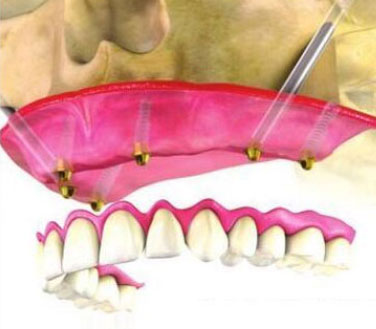

“穿颧种植”是一种通过颧骨固定种植牙的技术,将种植体植入到位于人面中部前,眼眶的外下方呈菱形较硬的骨头——颧骨,是当今难度很大的种植技术,被种植牙界誉为“珠穆朗玛峰”的顶级技术,俗称“无土栽培术”。一般重度颌骨吸收患者需要2颗穿颧种植体就可以获得很好的固位效果,在前牙区可以垂直植入2至3颗普通种植体。对于较度严重的颌骨吸收的患者,还可以使用四颗穿颧种植体。

“穿颧种植”受力效果好,稳定性强,不同于一般的种植牙技术,不仅大大缩短了种牙时间,避免或减少了术中大量植骨的风险,还具有实现即刻负重的优势,非常适用于上颌骨切除、上颌骨严重萎缩,常规内外提升也无法达到种植条件的无牙颌患者......查看详情